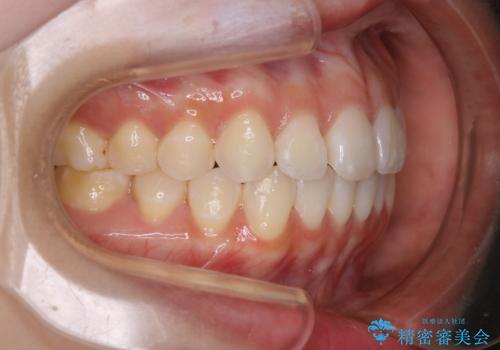

前歯で噛めない:オープンバイト(開咬)を非抜歯インビザラインで治療

- 上下の歯が噛んでいないことを気にしてご相談にいらした方です。

オープンバイトの方への治療は、通常抜歯を行いワイヤーによる矯正治療を行うことが多いですが、今回はインビザラインの特性を生かし、非抜歯にて綺麗な歯並びを作ることが出来ました。